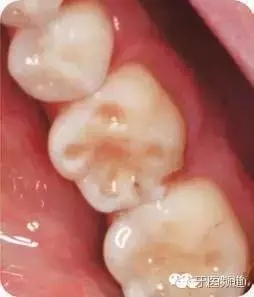

● 下后牙舌側(cè)牙齦輕度發(fā)紅,并伴有輕度探診出血(圖1,圖2)。

● 患者1個(gè)月前曾接受潔牙治療。可見少量齦上牙石,未探及齦下牙石。牙齒頸部及鄰面少量菌斑。沒有牙齦退縮,但是#24、25之間齦乳頭高度輕微喪失。探診深度見圖3,發(fā)現(xiàn)#19頰側(cè)根分叉10mm牙周袋伴探診出血,局部有膿液。其余部位探診均正常(圖4)。

圖4 咬合時(shí)左側(cè)下頜后牙口內(nèi)觀,#19根分叉處10mm牙周袋。